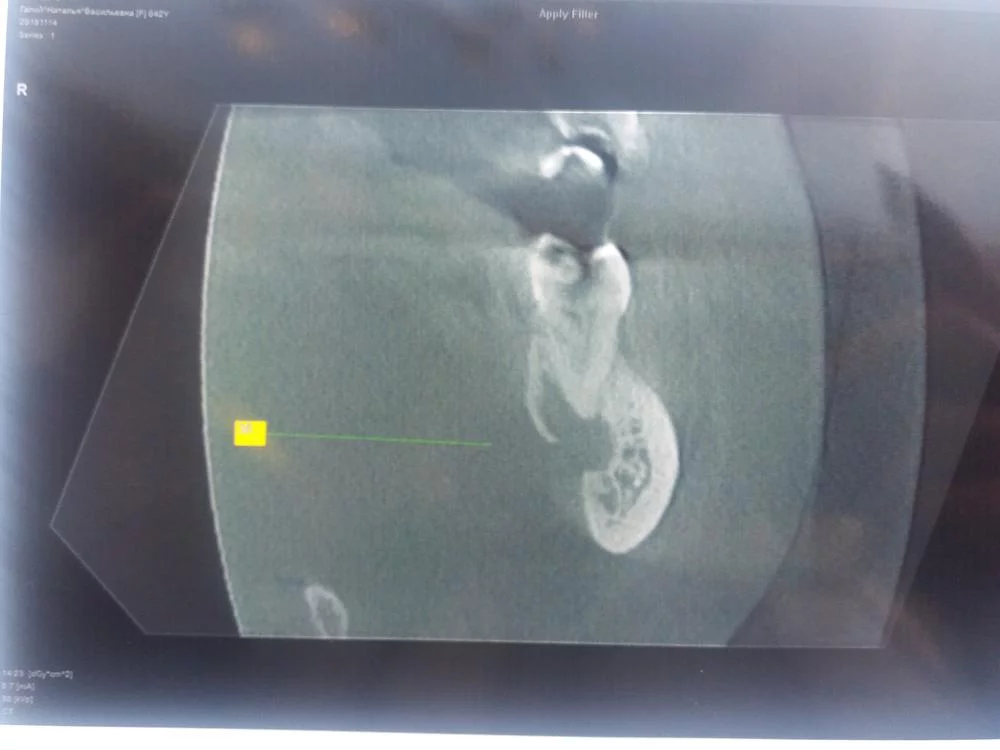

Пародонтолог в такой ситуации может не взяться. Считается, что случай запущенный.

А что же делать в такой ситуации ? Посоветуйте пожалуйста. Пока я прошла курс электрофореза, и чувствительност уменьшилась